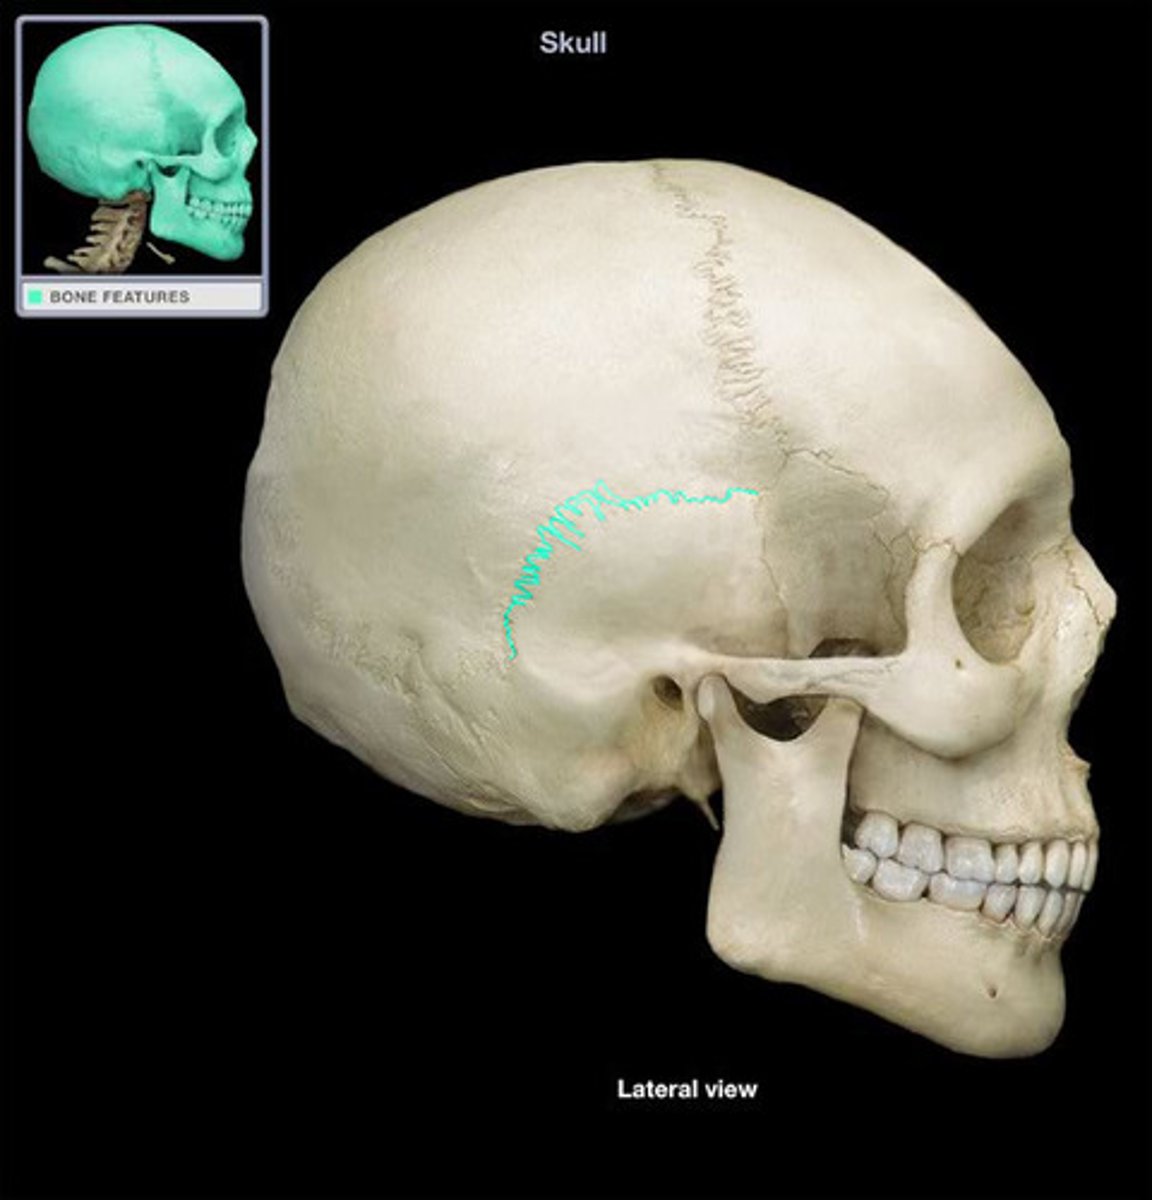

coronal suture

sagittal suture

lambdoid suture

squamous suture

suture

interlocking line of union between bones